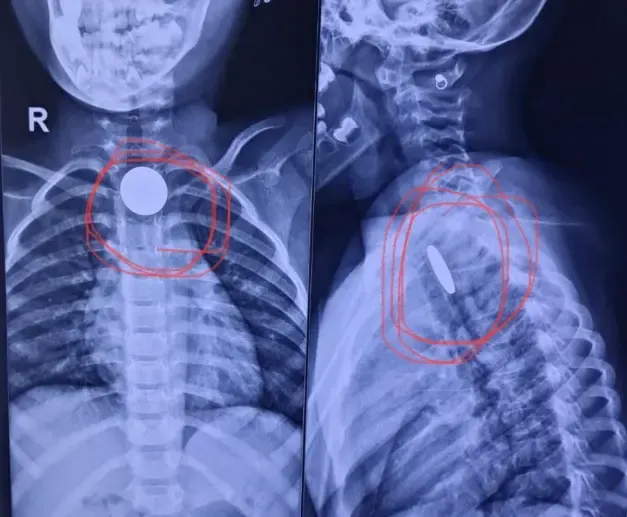

विभाग के प्रमुख डॉ. योगेश गज्जर ने बताया कि पहले मामले में एक दो वर्षीय बच्चे को गले में तेज दर्द और उल्टी की समस्या के साथ अस्पताल लाया गया था। जांच में पाया गया कि बच्चे की आहार नली में एक सिक्का फंसा हुआ था। यह स्थिति गंभीर थी, क्योंकि सिक्का श्वसन नली के निकट अटका हुआ था, जिससे सांस लेने में कठिनाई हो सकती थी। डॉक्टरों की टीम ने सफलतापूर्वक ऑपरेशन कर बच्चे की आहार नली से सिक्का निकाल लिया।

दूसरा मामला साढ़े चार साल की एक बच्ची का था, जिसने खेल-खेल में सिक्का निगल लिया था। थोड़ी देर बाद बच्ची को गले में दर्द और खाना निगलने में मुश्किल होने लगी। उसके परिजन उसे सिविल अस्पताल ले गए, जहां ईएनटी विशेषज्ञों ने एक्स-रे द्वारा स्थिति की पुष्टि की। डॉक्टरों ने सावधानीपूर्वक बच्चे की आहार नली से सिक्का निकाला।